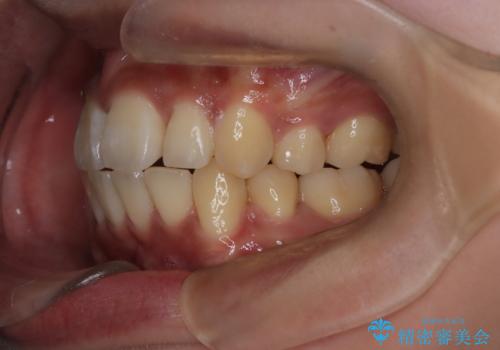

前歯の前突と口元の突出感を改善|上下左右4番抜歯+審美ワイヤー矯正

- 前歯の突出が強く、口元が前に出ている印象を改善するため、上下左右の第一小臼歯(4番)を抜歯する矯正治療を計画しました。抜歯により得られたスペースを利用して、前歯を後方へと移動させて整列します。治療には目立ちにくい透明な審美ブラケットとワイヤーを使用し、毎月1回の調整を行いながら徐々に歯を動かし、約2年で口元全体を整える計画としました。

前歯が前に出ているため口元が突出し、唇が閉じにくいなどの悩みを抱えておられました。治療にあたり上下左右の第一小臼歯を抜歯し、十分なスペースを作ることで前歯を効果的に後方へ移動させました。装置には透明で目立ちにくい審美ブラケットを採用し、治療中の審美的ストレスを軽減しました。定期的な調整を通じて無理なく確実に歯列を整え、前歯の突出感を解消。治療後は口元の印象が自然で美しく改善され、患者様には非常にご満足いただけました。